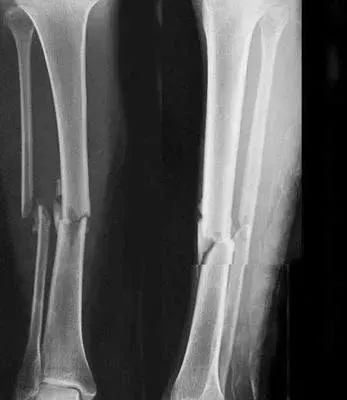

5、小腿踢球時(shí)骨折過(guò),還能當(dāng)兵嗎?

四肢單純性骨折,治愈1年后,X線片顯示骨折線消失,復(fù)位良好,無(wú)功能障礙及后遺癥(空降兵除外),合格。